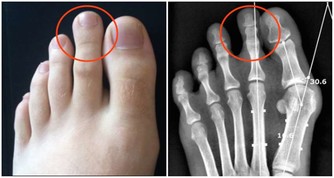

此外還含豐富的磷與鈣,對促進骨骼的正常發育,預防佝僂病,幫助正常長牙都是很有好處的。 改善肝臟功能,有助於抵禦風濕性疾病和痛風 萵筍含有少量的碘元素,它對人的基礎代謝、心智和體格發育甚至情緒調節都有重大影響,因此萵筍具有鎮靜作用,經常食用有助於消除緊張,幫助睡眠。 2 開通疏利,消積下氣 萵苣味道清新且略帶苦味,可刺激消化酶分泌,增進食慾。 其乳狀漿液,可增強胃液、消化腺的分泌和膽汁的分泌,從而促進各消化器官的功能,對消化功能減弱、消化道中酸性降低和便秘的病人尤其有利。 3 增進食慾 萵筍中還含有萵苣素、乳酸、蘋果酸、天門冬鹼、琥珀酸、甘露醇等。 萵筍的漿液十分豐富,味道清新,略帶苦味,能刺激消化,增加膽汁分泌量,刺激消化道各器官蠕動,有助於增進食慾。